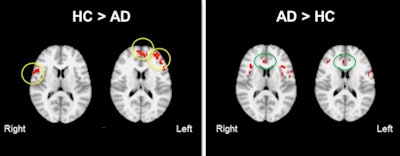

Overall, the patients with early Alzheimer's disease showed significantly greater activation in the bilateral prefrontal cortex, including the dorsolateral and ventrolateral prefrontal cortex, as well as in the anterior cingulate cortex, compared with the controls.

Brain activation patterns were most noticeably different between the Alzheimer's subjects and the healthy controls when the encoding and retrieval tasks were being performed.

"We see that the regions of increased perfusion are at the right prefrontal cortex, helping the Alzheimer's disease patients with the executive control of their brain, and may be due to how these patients in the early stages of Alzheimer's are compensating during the retrieval task," he said.